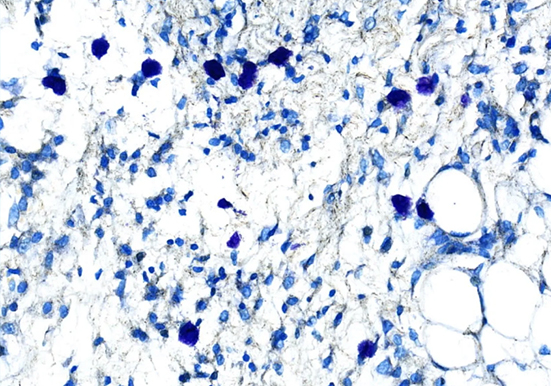

肥大细胞染色

肥大细胞染色是一种病理学检查方法,用于检测组织中肥大细胞的数量、分布和形态等情况,对多种疾病的诊断和研究具有重要意义。以下是一些常见的肥大细胞染色方法:甲苯胺蓝···

甲苯胺蓝染色

以下是关于甲苯胺蓝染色的详细介绍:染色原理化学结构基础:甲苯胺蓝属于醌亚胺染料类,含有两个发色团(胺基和醌型苯环)和两个助色团。助色团促使染料电离成盐类,帮助发···